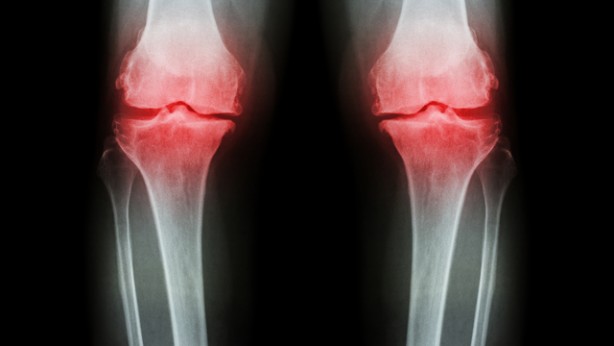

Kemik erimesine bağlı kırıkların en çok kalça, bel ve bilek kemiklerinde görüldüğünü vurgulayan Uzm. Dr. Esra Tutal, “Osteoporoz hem kadınları hem de erkekleri etkileyen bir hastalıktır.

Kemik erimesi omurlarda, el bileğinde ve kalça kemiğinde kırılmalara yol açarak sakatlıklara hatta ölümlere yol açabilir” şeklinde konuştu.

Günlük düzenli yapılan egzersiz (yürüyüş gibi) kemiklerin güçlenmesini sağlar. 65 yaş üstü kadınlar, 70 yaş üstü erkekler ve risk faktörü olanlar ise daha erken yaşlardan itibaren her yıl düzenli olarak kemik taraması (kemik mineral dansitometri) yaptırıp, henüz kırık oluşmadan tanı konulabilirse hastalığın tedavisi mümkündür.”